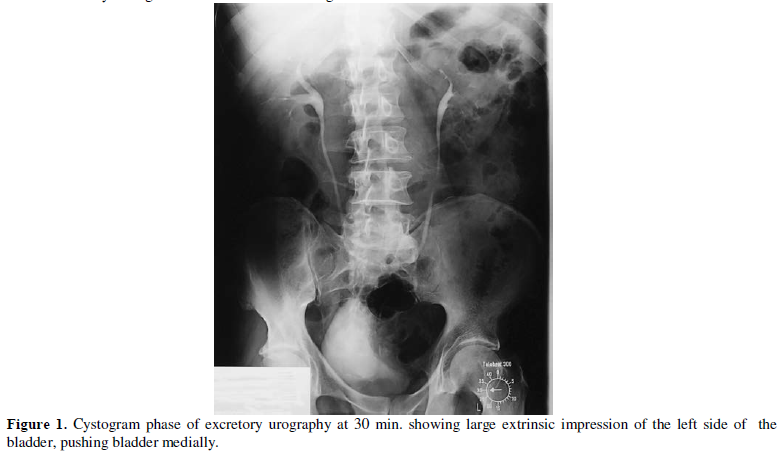

hematuria. Urinary cytology revealed porely differentiated tumor. The cytogram

phase of excretory urography showed large extrinsic impression of the left side

of the urinary bladder (Figure 1) A CT scan of the pelvis (Figure